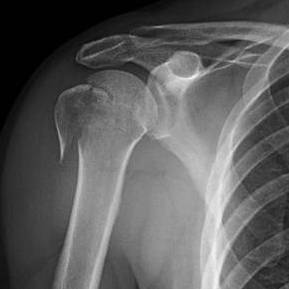

Oh no ! That’s really brave of you . I had a rotator cuff surgery in October 2019 and it took me a whole year before my arm got back it’s full movement. Even now I get the occasional twinge and my arm gets tired with extra work ..\. Take care and do your Physio regularly. That really helps